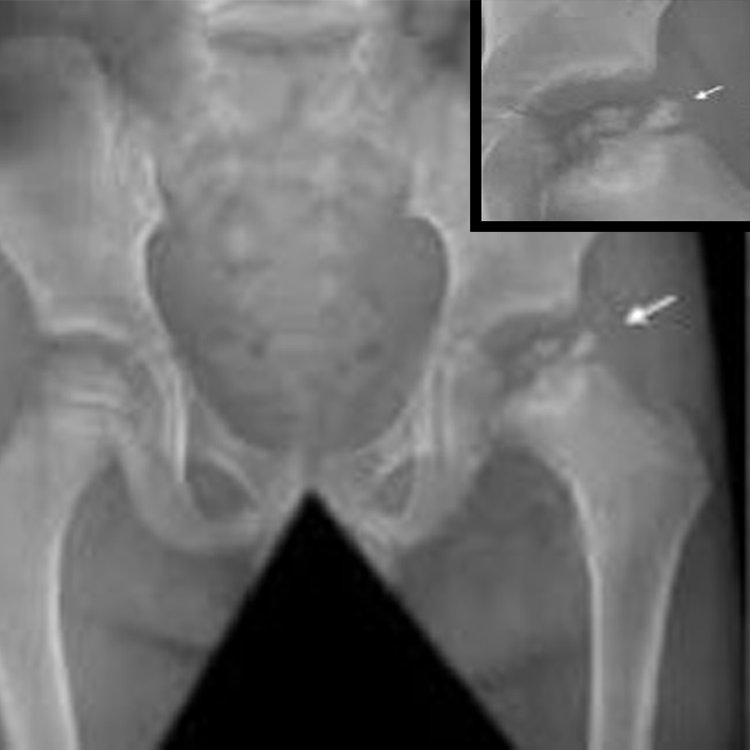

انزلاق رأس الفخذ SCFE

داء ليغ كالفيه بيرثيز

خلع الورك الولادي